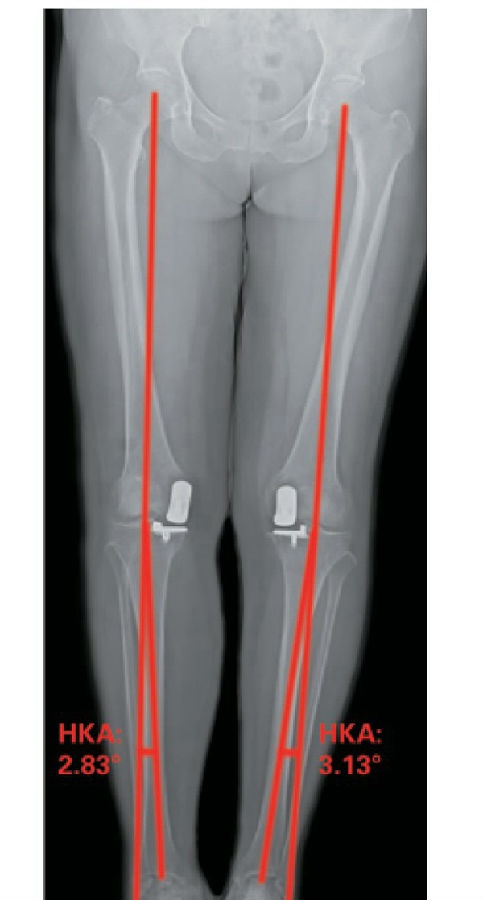

病例(1)65岁女性患者,因双膝关节疼痛伴活动 受限5年余入院。行双膝关节正侧位X线片可见典型前内侧骨关节炎表现,术前双下肢内翻排列,右膝HKA为4.26°,属于轻度内翻,左膝HKA为7.42°,属于中度内翻。术后3个月复查下肢力线右膝HKA为2.83°,左膝HKA为3.13°,较术前改善,手术前后影像学资料见图1~3。

图3术后3个月站立位双下肢全长X线片示右膝HKA为2.83°,左膝HKA为3.13°